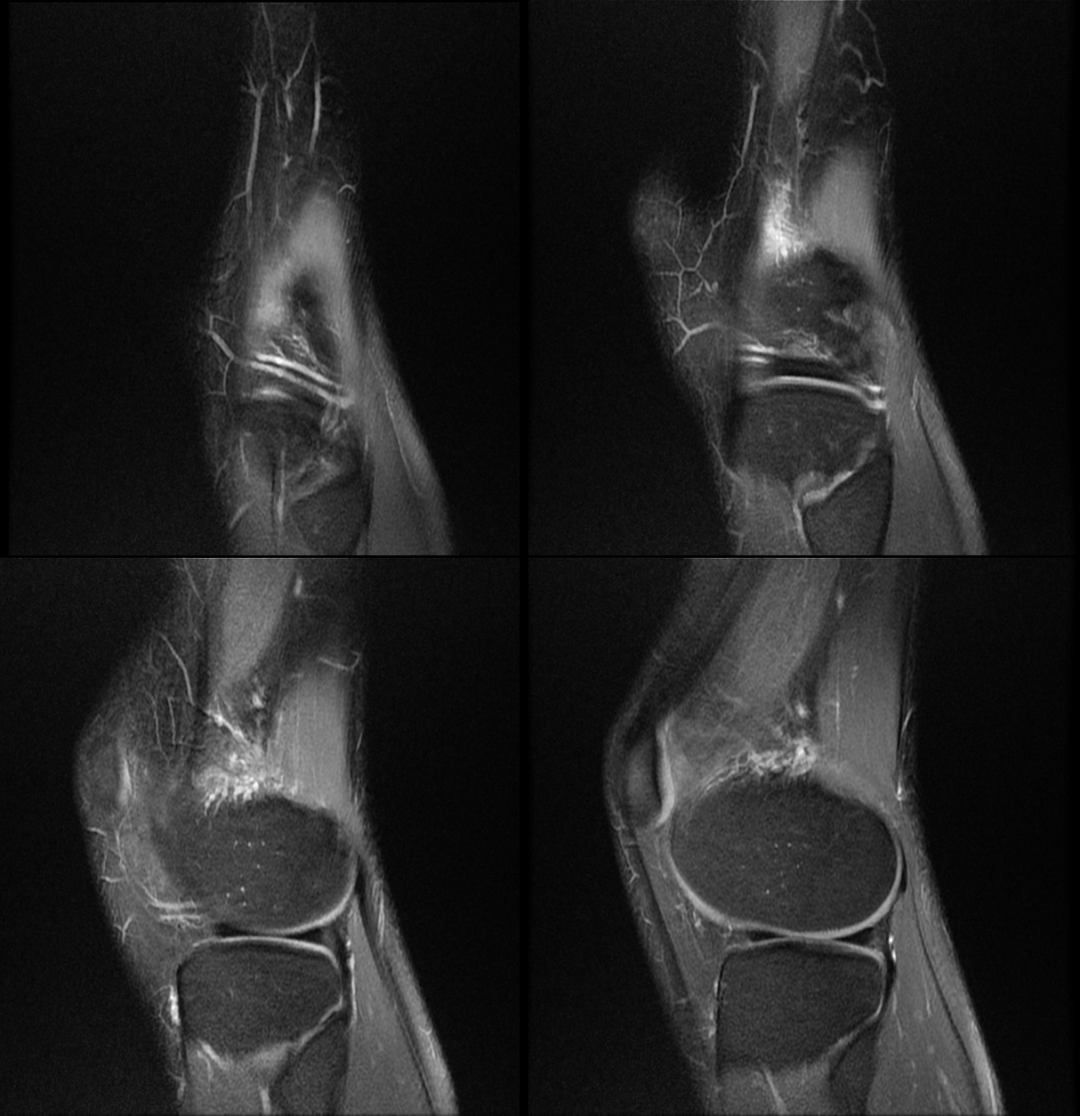

“跑步膝”病例展示

患者,女性 ,24 岁

主诉:右膝关节外侧反复疼痛不适半年余,近一个星期疼痛加重。现病史:患者右膝关节外侧间歇性疼痛不适半年余,近一个星期疼痛加重,屈膝时明显,门诊行膝关节 X 线片检查,未见明显异常。患者否认手术史/外伤史。为进一步明确情况,我们建议患者行膝关节磁共振检查;图像如下:T1

T2 压脂

冠状位

轴位

大家是否发现什么异常?该患者是膝外侧疼痛不适的症状,我们重点观察了外侧半月板及外侧副韧带,但是我们发现是正常的;

但是我们发现有一个地方信号不对;

大家发现了没有?那这是什么呢?

那么我们刚刚看到信号增高的就是髂胫束,排除了半月板和外侧副韧带的问题,那么膝关节外侧疼痛是不是这个原因导致的呢?

影像学表现

1 T2WI PD 序列上可以显示靠近股骨外侧髁与髂胫束之间的信号增高,边界不清,外侧滑膜增厚;

2 髂胫束靠近股骨外侧髁水平出现增厚改变,部分严重患者可以出现连续性中断;3 髂胫束表面或深部信号明显增高;4 可伴股骨外侧髁反应性骨髓水肿